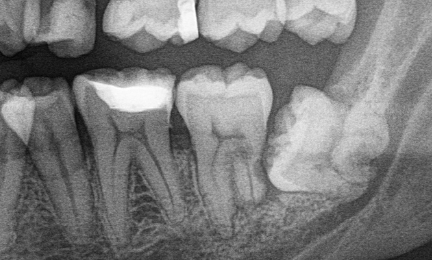

A fogászati szárnyas röntgen (Bite-wing) alkalmas a fogak közötti vagy a tömések alatti fogszuvasodás feltárásában, amelyek szabad szemmel nem láthatóak.